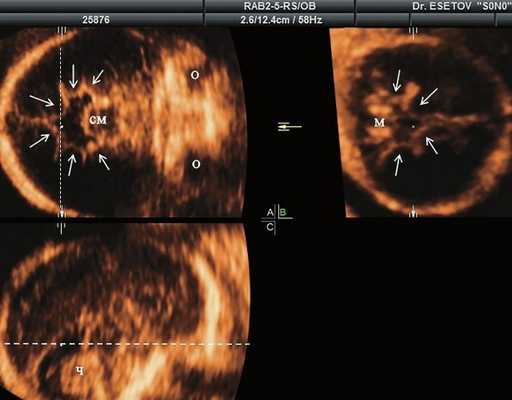

а) Ультразвуковая трехмерная реконструкция (СМ - средний мозг, О - орбита, Ч - червь, М - мозжечок). На плане А показан нижнеаксиальный срез на уровне среднего мозга и орбит, показывающий аномальную бороздчатость медиальной поверхности височных долей (стрелки). Уровень получения этого среза отражен пунктирной линией на плане С. На плане B показан коронарный мозжечковый срез, на котором также отражены выпуклые извилины медиальной поверхности височных долей (стрелки). Пунктирная линия на плане А показывает уровень получения коронарного среза.

| Набл. 1. 24,3 нед. | БПР - 25,3 нед. ОГ - 24,6 нед. Аномально повышенная бороздчатость и выпуклость извилин нижнемедиальной поверхности височных долей (рис. 1а). | Торакоабдоминальное соотношение - 66,7% (рис. 1б) Длина ребра - среднее для 16 нед. | Бедренная кость 19,6 мм (47,8% от должной), изогнута ("телефонная трубка") (рис. 1в). Остальные кости - среднее для 15 нед. | Уплощенные тела поясничных позвонков. |

В наблюдениях 1-3 наличие изогнутой бедренной кости (по типу "телефонной трубки") (рис. 1в, 2г, 3г) позволяло предположить наличие ТД I типа. Целе направ ленное исследование головного мозга этих плодов в дополнение к описанным скелетным признакам показало и картину ДВД. Была выявлена аномально повышенная бороздчатость и выпуклость извилин нижнемедиальной поверхности височных долей у плодов в наблюдениях 1-3 (рис. 1а, 2б, 3б). Это позволило установить диагноз ТД I типа.